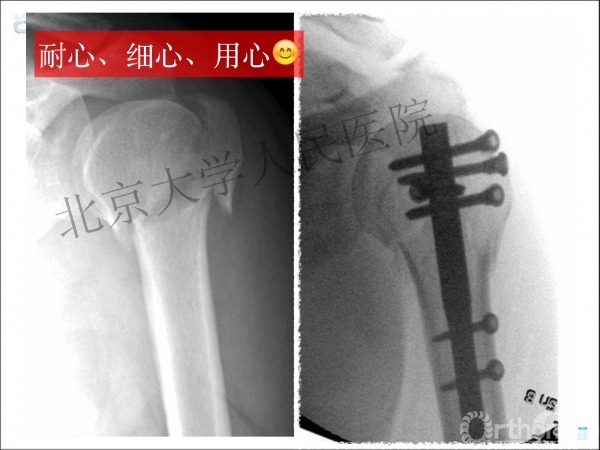

复位良好的标准:颈干角:135°,大结节与肱骨头距离:8mm

术后3月随访:继发性颈干角变小22°(5-82),肱骨头内翻,达46%

严重影响了患者的生活质量

进钉更完美——我们的帮助